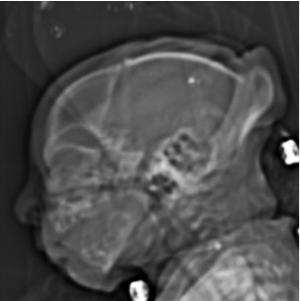

Figure 4. Images obtained in the case of an 18-year-old woman, first seen for rash at 10 weeks of pregnancy, with confirmed Zika virus infection. US findings obtained at 20 weeks of gestational age were reportedly normal, with normal head circumference of 17.5 cm. At 37 weeks of gestational age, (a) sagittal transvaginal and (b) coronal transabdominal US images obtained with the head upside down show a small head circumference (26.4 cm, corresponding to 28 weeks 5 days, below the 3rd percentile), moderate ventriculomegaly with dense intracranial calcifications (arrowheads on a), and abnormal head shape with flattened appearance and thickened skin (arrow on a). On the sonogram, it is difficult to precisely localize the calcifications, given the thin parenchyma. (c, d) Axial bone window CT images, (e) sagittal localizer CT image, and (f–h) axial CT images show microcephaly with cerebral atrophy, and, despite ventriculomegaly, the extra-axial cerebrospinal fluid spaces are still prominent. The hypoattenuating calcifications are predominantly located in the subcortical white matter at the gray matter–white matter interface. There is markedly abnormal skull shape with some eversion of the bones at the suture sites (particularly frontoparietal sites), with redundant skin folds (particularly in the parieto-occipital region). (i) Sagittal T1-weighted, (j, k) coronal T2-weighted, and (l) axial susceptibility-weighted MR images obtained at 1 month of age show an undersegmented midbrain, severe microcephaly, open sylvian fissures, and polymicrogyria. The dense calcifications are evident on the susceptibility-weighted image. On the sagittal images (a, e, i), note the small supratentorial compartment and associated skull deformity.